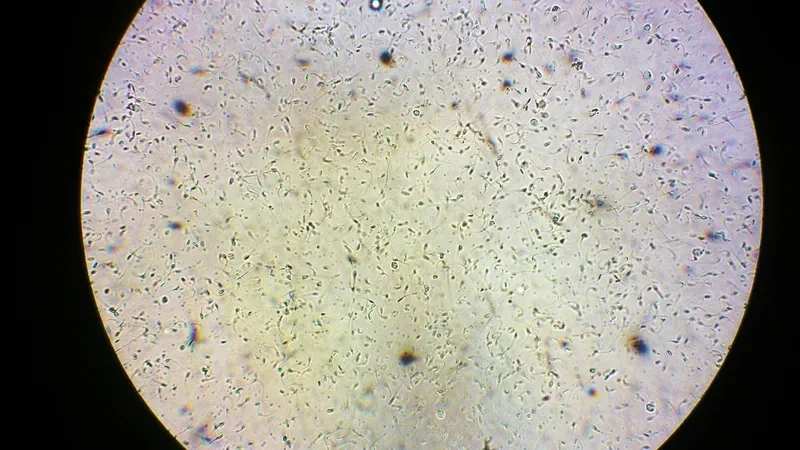

Tinh trùng dưới kính hiển vi là một cảnh tượng sinh học kỳ thú, đồng thời là hình ảnh cốt lõi trong xét nghiệm tinh trùng (tinh dịch đồ). Việc kiểm tra tinh trùng giúp đánh giá khả năng sinh sản của nam giới.

Cấu tạo của tinh trùng dưới kính hiển vi được chia thành ba phần chính: đầu, cổ và đuôi. Phần đầu chứa nhân và enzyme acrosome, cần thiết cho quá trình thụ tinh. Phần đuôi dài và mảnh giúp tạo ra chuyển động để di chuyển về phía trứng.

Khám phá những hình ảnh tinh trùng dưới kính hiển vi trong bộ sưu tập này sẽ cho thấy sự khác biệt rõ rệt giữa hình thái tinh trùng bình thường với tinh trùng dị dạng.